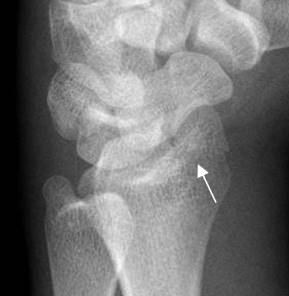

Fig 184. Fractura de Chauffeur.

A y B: Rx AP de muñeca. C: RM coronal en STIR. Fractura intra-articular y en sentido oblicuo, en la parte lateral del radio distal.